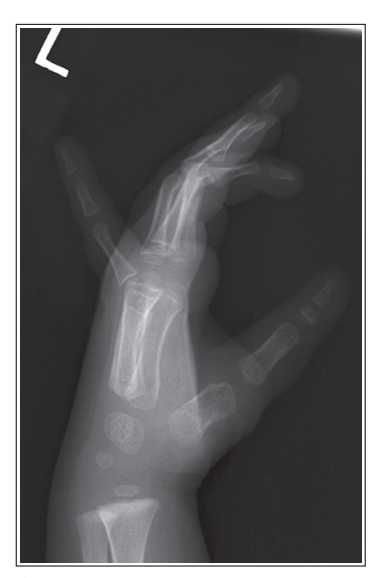

What’s wrong with this oblique finger projection?

Foreshortening of distal phalanx

Finger was not flexed